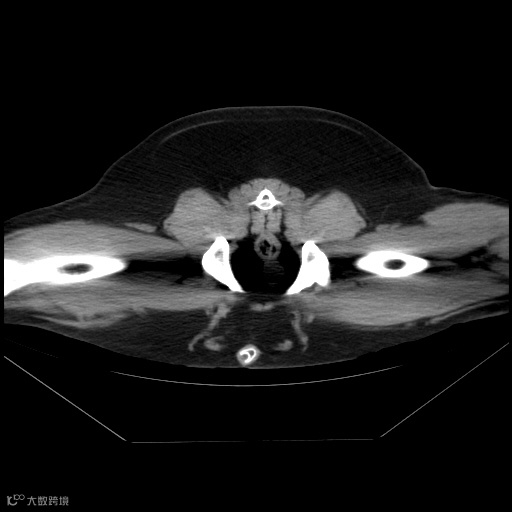

充分了解动物的结构解剖学,包括各个器官和组织的位置、形态和特征。正确评估扫描图像质量对于准确判读至关重要。

是确保诊断区域图像质量的关键因素。标准的摆位减少断层图像的变形,利于直接诊断,同时减少非诊断区域对诊断区域的干扰和导致的部分伪影。

双后肢未拉直

影响髋部观察